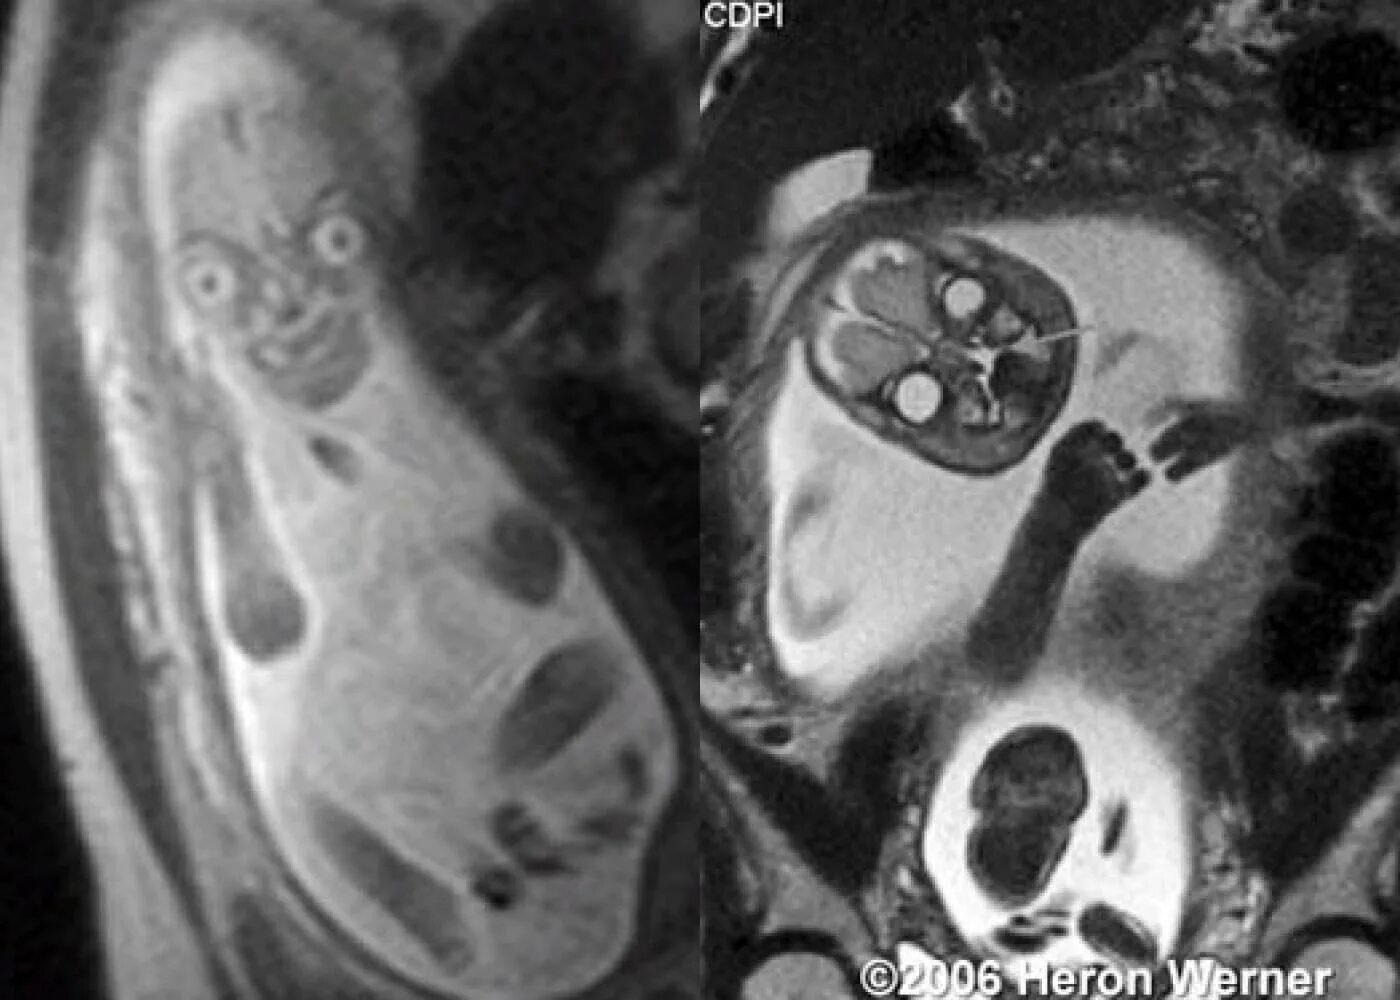

Мрт беременной